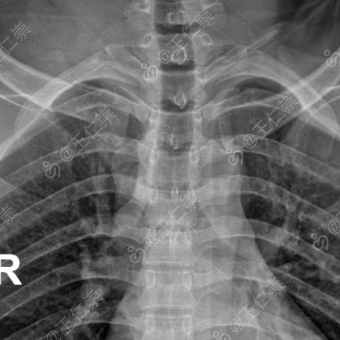

影像学检查

:胸部 X 光片是首选筛查方法,可明确骨折数量、部位及移位情况,同时排查气胸、血胸;胸部 CT(尤其是三维重建)对隐匿性骨折(如裂纹骨折)、多根多处骨折及合并肺损伤的诊断更精准,是制定治疗方案的重要依据;